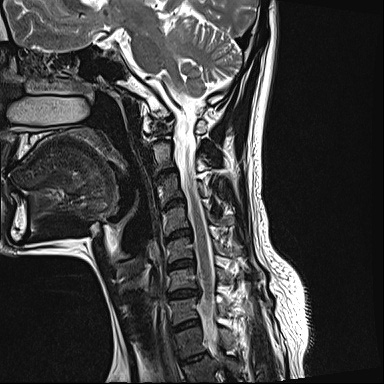

Ű 177 64 40 ()ijħ ڸǥغ ǥغ ϱ ȣϴ 1C.ٸǷ 6C.ڸ 6C.ھ Ḳ 6C.ڻ ()ũ( ߰Ż) ڸ(߹) ĿCڸ(ĸ) Ը ũ(߰Ż)ġ, , Ḳ ġ Ǵ ġ ()ijħ ڸǥغ ǥغ ϰ ߴ ġ 2008~2011 ð ɾƼ ǻ ۾ Ҷ, Ʈ , ȸ ϰ, . 2011 4 : 6,7 ߰Ż , ڸ ó ļ ַ ġ . ü, ߳, ѹ, ũ, ֻġ ġ غ ȿ ġ ġᰡ Ұ Ǵϰ ֿ 3ȸ ƮĪ ణ ȣ. 2014 5 20 濡 ħ ڱ ϰ · ư. (ֱ ϰ, Ʈ ϰ ) а ũ ִ ֺ, Ʒ κп δֻ 1ȸ ̰, ణ . ûϸ鼭 ȸԲ ϴ ûϰ ߽ϴ. Ϻϰ ȸ ּ. mriԴϴ. |